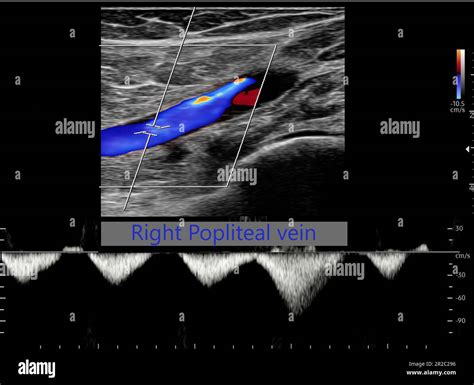

• Color Doppler Ultrasound: Uses color mapping to show the velocity and direction of blood flow, identifying areas where blood flow is restricted or absent due to an obstruction.

During the examination, the technician employs a technique called compression ultrasonography. By applying gentle pressure with the ultrasound probe, the examiner assesses whether the vein collapses. A healthy, patent vein will collapse completely under pressure, whereas a vein containing a thrombus will remain rigid and fail to compress, serving as a primary diagnostic indicator of a clot.

• Compressibility: Whether the vein is fully compressible at all levels.

• Visualization of the Thrombus: The presence of echoes within the vein lumen.

• Augmentation: The increase in blood flow response when pressure is applied to the limb, which confirms the absence of obstruction.

• Spontaneity and Phasicity: Normal venous blood flow should be spontaneous and change with the patient’s breathing cycle.